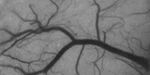

Clinical Speckle Imaging

We are designing and building translational laser speckle contrast imaging systems for clinical applications such as continuous blood flow monitoring during vascular neurosurgery.